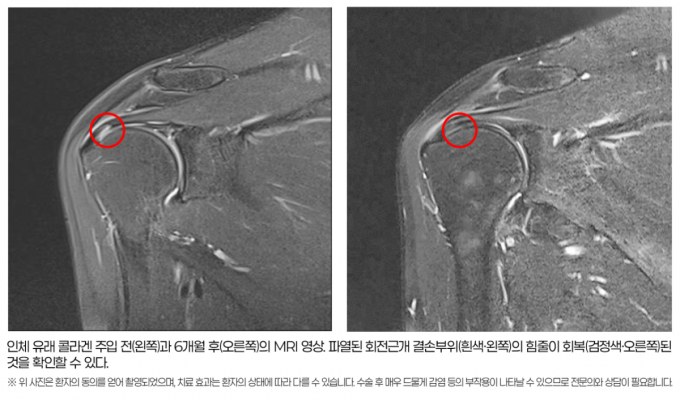

À̹ø ¿¬±¸ÀÇ °¡Àå Å« ¼º°ú´Â MRI¸¦ ÅëÇØ ÈûÁÙÀÇ ±¸Á¶Àû ȸº¹À» Á÷Á¢ È®ÀÎÇß´Ù´Â Á¡ÀÌ´Ù. 6°³¿ù ÈÄ MRI ÃÔ¿µ¹°À» ºÐ¼®Çß´õ´Ï ȸÀü±Ù°³ ¼Õ»ó ÁöÇ¥ÀÎ ½ÅÈ£°µµÀÇ È£Àü ¹× ÆÄ¿ ºÎÀ§ÀÇ Àç»ýÀÌ 1§® ÀÌ»ó ³ªÅ¸³ ȯÀÚ°¡ 83.33%(30¸í Áß 25¸í)¿¡ ´ÞÇß´Ù. ÆÄ¿ ºÎÀ§°¡ 2§® ÀÌ»ó ÁÙ¾îµç ȯÀÚµµ 26.66%(30¸í Áß 8¸í)¸¦ Â÷ÁöÇß´Ù.